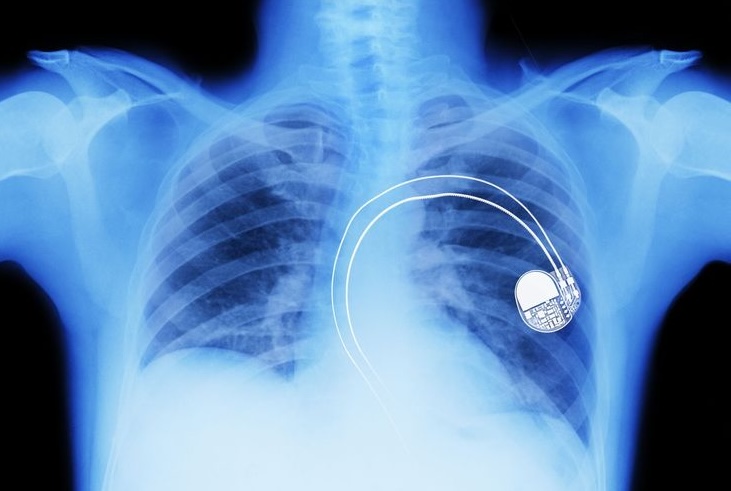

Pacemaker PH Pinterest

Questa non è la sceneggiatura di un thriller high-tech. È la vulnerabilità più terrificante e intima dell’era moderna. È l’assassinio tramite Wi-Fi, e il proiettile è un dispositivo nato per salvare vite: il pacemaker.

Per decenni, dispositivi medici come pacemaker, defibrillatori impiantabili (ICD) e pompe di insulina sono stati sistemi chiusi. Ma oggi sono “smart”. Sono dotati di connettività wireless (Radio Frequenza o Bluetooth) per uno scopo nobile: permettere ai medici di monitorare i pazienti e regolare i dispositivi da remoto, senza bisogno di interventi chirurgici invasivi.

Questa comodità, però, ha creato una falla catastrofica. Quella connessione è una porta. E come ogni porta, può essere forzata.

Un hacker, con le giuste conoscenze e un’antenna specializzata, può “agganciare” il segnale del dispositivo a distanza. Non serve essere nella stessa stanza; a seconda della tecnologia, basta essere nello stesso edificio, o in un’auto parcheggiata fuori.